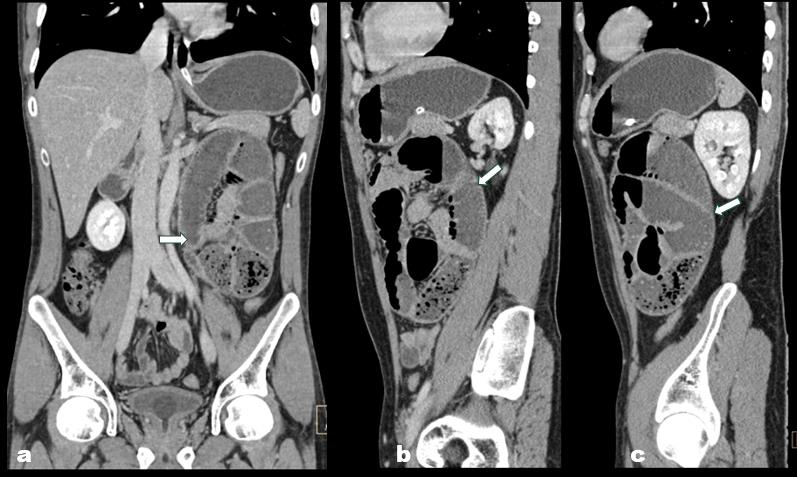

Figure 3: ((a: Coronal; b & c: Sagittal):Coronal and sagittal CECT

abdominal images show a cluster of dilated jejunal loops in the left

paraduodenal region. The loops within the hernia sac appear crowded

while maintaining normal wall thickness and enhancement. The white arrow

indicates the hernia sac containing the dilated jejunal loops.